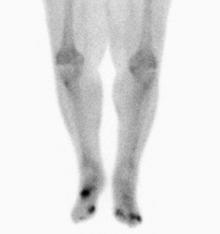

Osteomyelitis in both feet as seen on bone scan

Nuclear medicine scans can be a helpful adjunct to MRI in patients who have metallic hardware that limits or prevents effective magnetic resonance. Generally a triple phase technetium 99 based scan will show increased uptake on all three phases. Gallium scans are 100% sensitive for osteomyelitis but not specific, and may be helpful in patients with metallic prostheses. Combined WBC imaging with marrow studies have 90% accuracy in diagnosing osteomyelitis.[23]